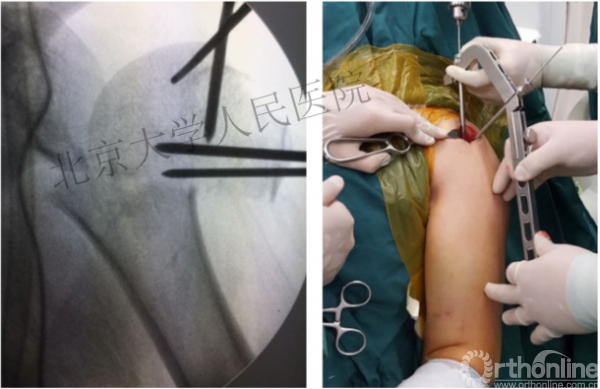

进钉更完美——我们的帮助

术中片